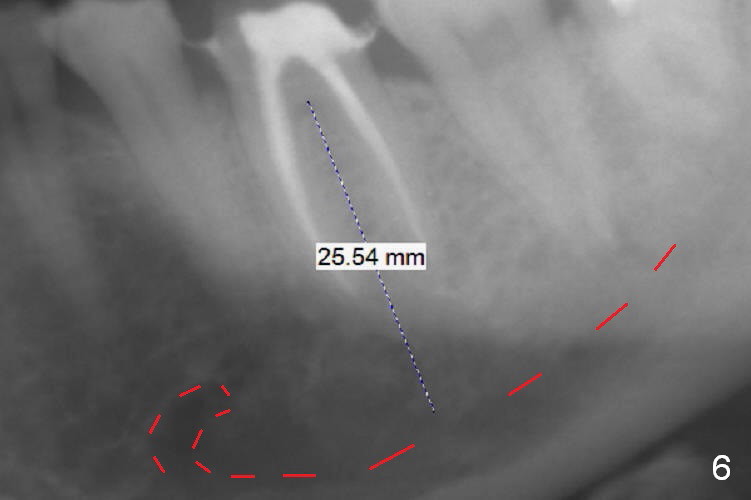

A 59-year-old woman had root canal therapy for the tooth #19 10.5 years ago (Fig.1 (red dashed line: the superior border of the Inferior Alveolar Canal). Two years later there was apparent periapical radiolucency with the distal root (Fig.2 *). The tooth remains asymptomatic until the last six months. There are 2 fistulae associated with the tooth: mesiolingual and buccal furca. Radiogra-phically, there are 2 radiolucent lesions: mesial and apical to the mesial root (Fig.3 *). If a 16 mm implant is placed, there will be approximately 5 mm apical bone (Fig.4); 7 mm for a 18 mm implant. The bone height is 25 mm (Fig.6). Therefore, once initial osteotomy is established with a 13 mm long drill with PA confirmation, the osteotomy is extended to its depth with 1.5x21 mm drill (Fig.5). After socket treatment with Metronidazole gauze with Epinephrine (1: 50,0000), take PVS impression of the socket to catch the large mesial defect. A fair amount of allograft and Osteogen is expected. It has been 9 months since last visit. Retake PA before surgery. If the mesial defect enlarges, start osteotomy in the distal slope of the septum.